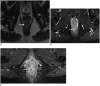

Although a rare disease, anal cancer is increasingly being diagnosed in patients with risk factors, mainly anal infection with the human papilloma virus. Magnetic resonance imaging (MRI) with external phased-array coils is recommended as the imaging modality of choice to grade anal cancers and to evaluate the response assessment after chemoradiotherapy, with a high contrast and good anatomic resolution of the anal canal. MRI provides a performant evaluation of size, extent and signal characteristics of the anal tumor before and after treatment, as well as lymph node involvement and extension to the adjacent organs. MRI is also particularly helpful in the assessment of complications after treatment, and in the diagnosis for relapse of the diseases.